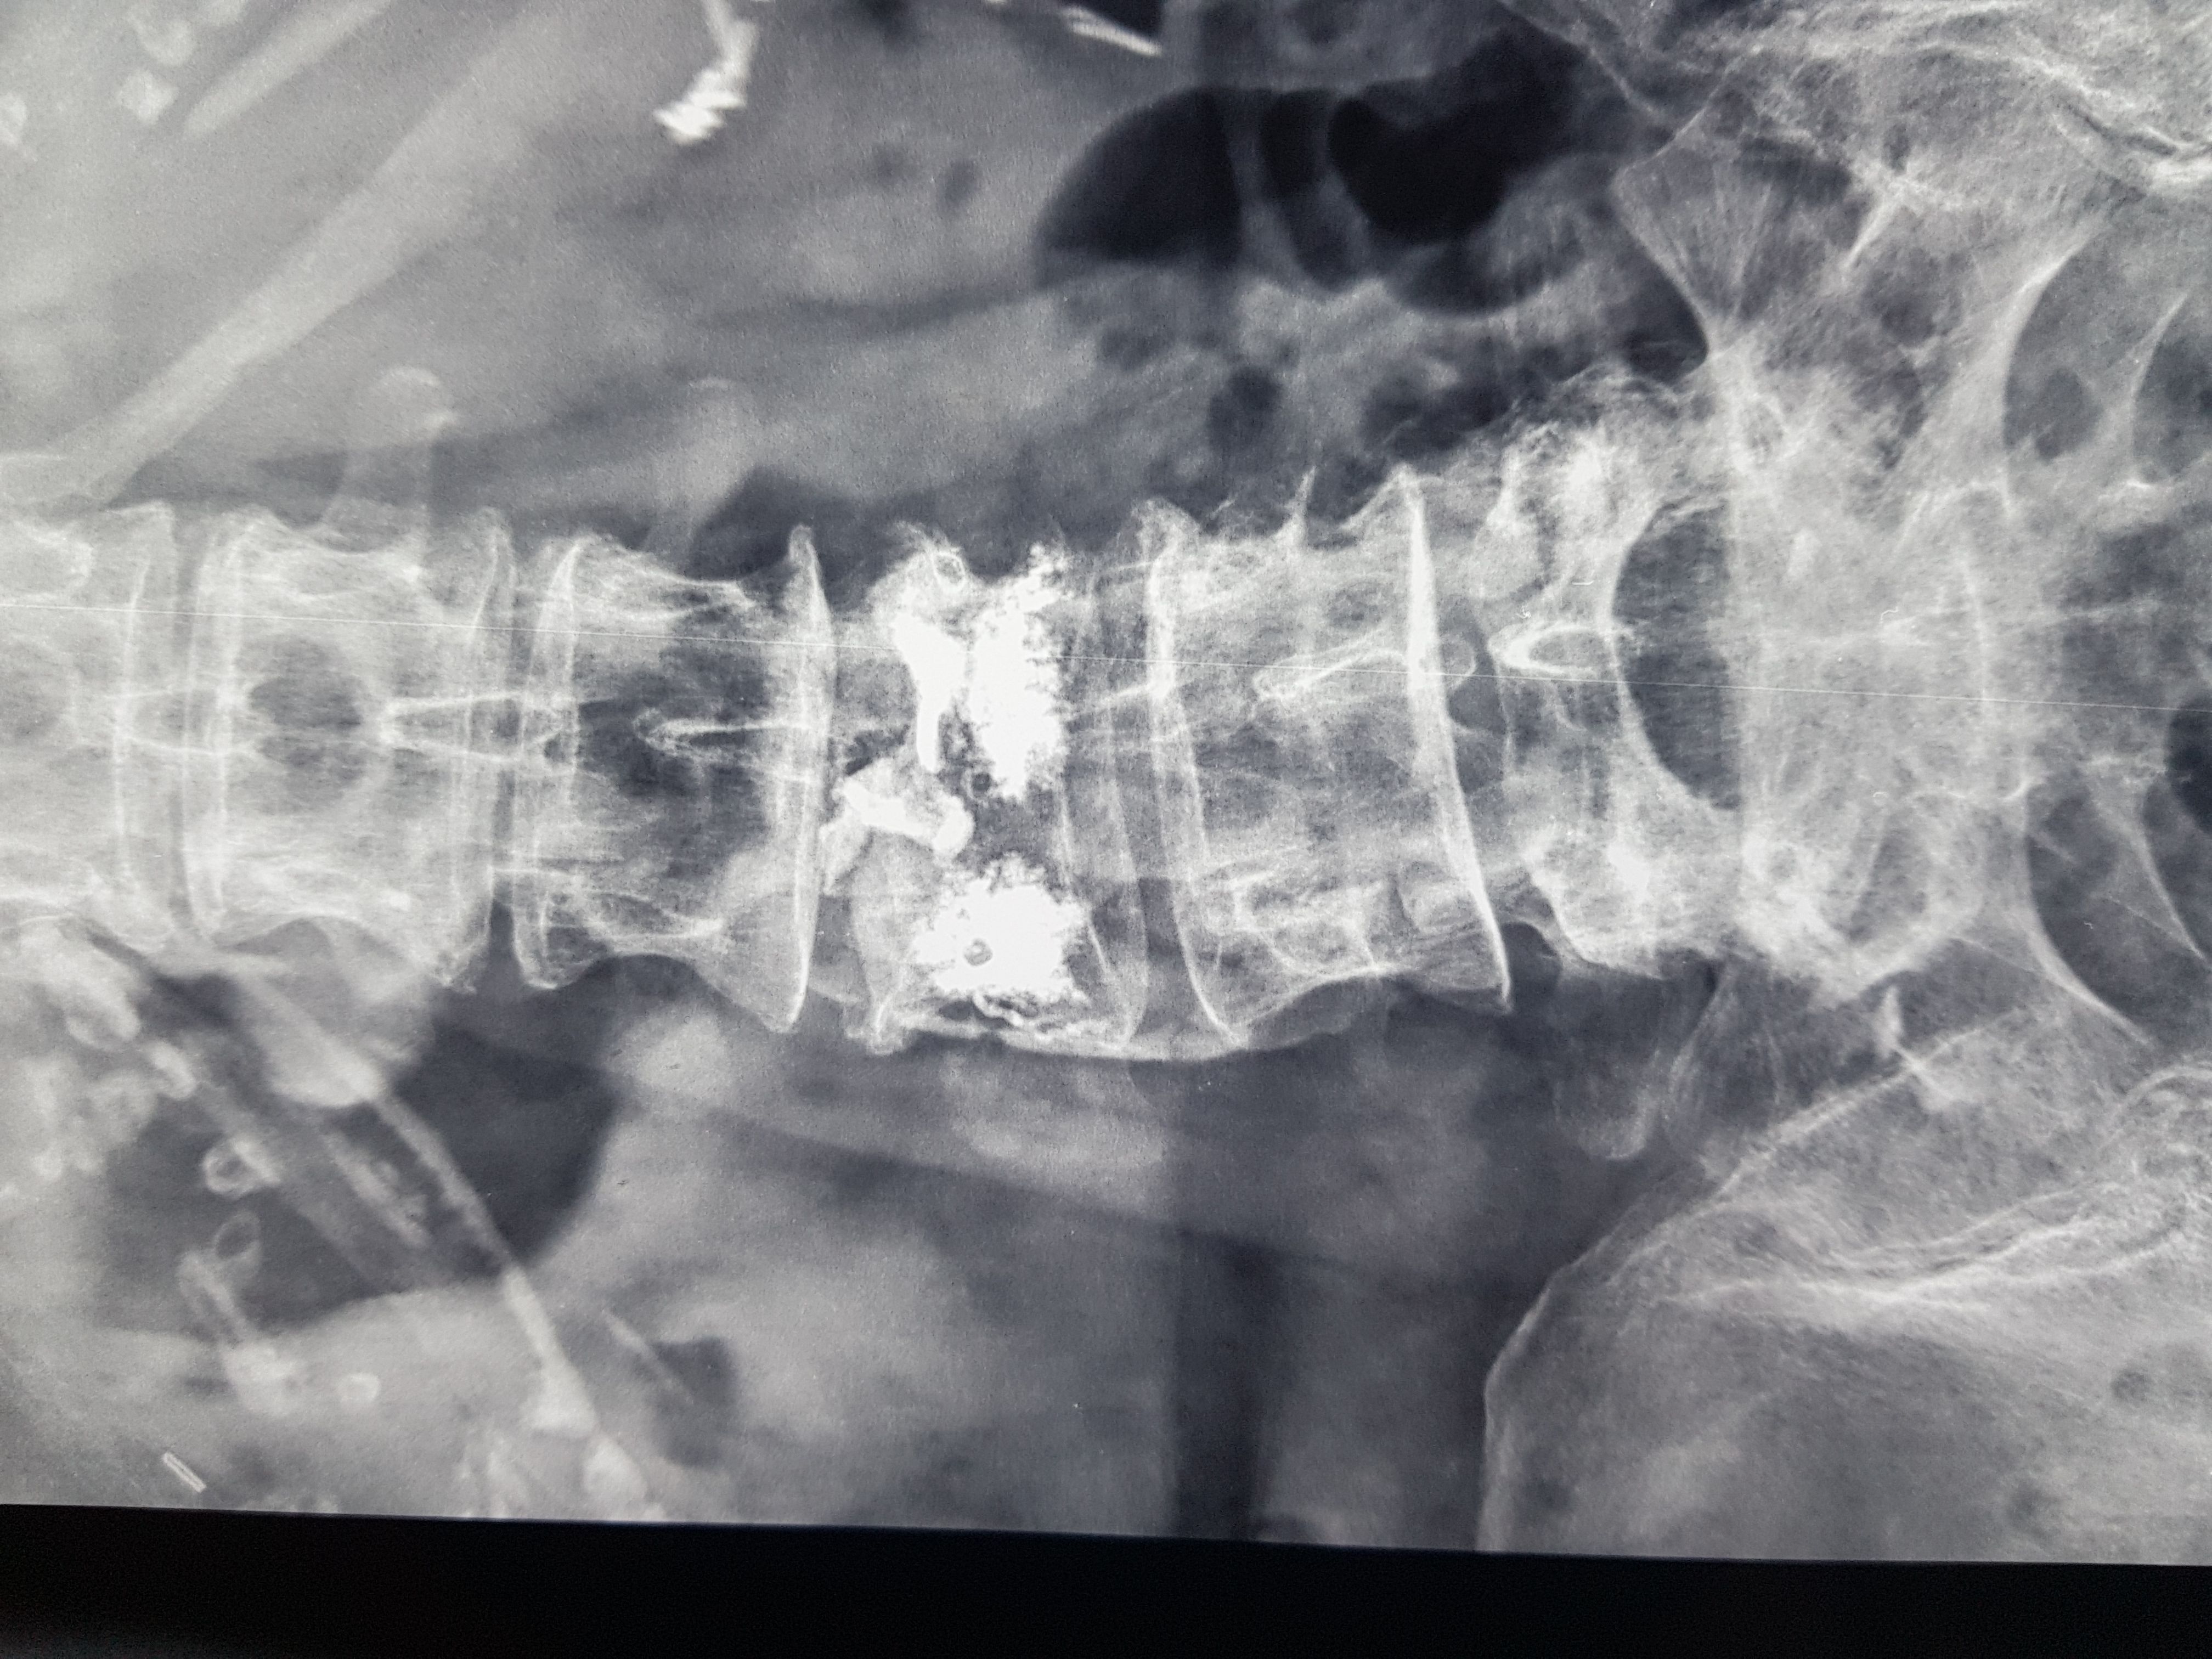

It is a minimally invasive technique with a 3 mm skin incision in which a balloon is inserted and creates a cavity in the fractured vertebra. A special material (PMMA) is then injected into the vertebra , restoring its morphology and passing the pain. The procedure takes 30-45 min and the patient is mobilized the same day. Usually the elimination of pain is immediate. The same operation is also indicated in cases of vertebral fractures from myeloma or other tumours (metastatic disease). The probability of complications is considered very low 1-4%. In the following photos you can see the procedure of balloon dilation in the vertebra and the subsequent injection of the sclerosing material.

Postoperative radiograph of a patient with an osteoporotic fracture.